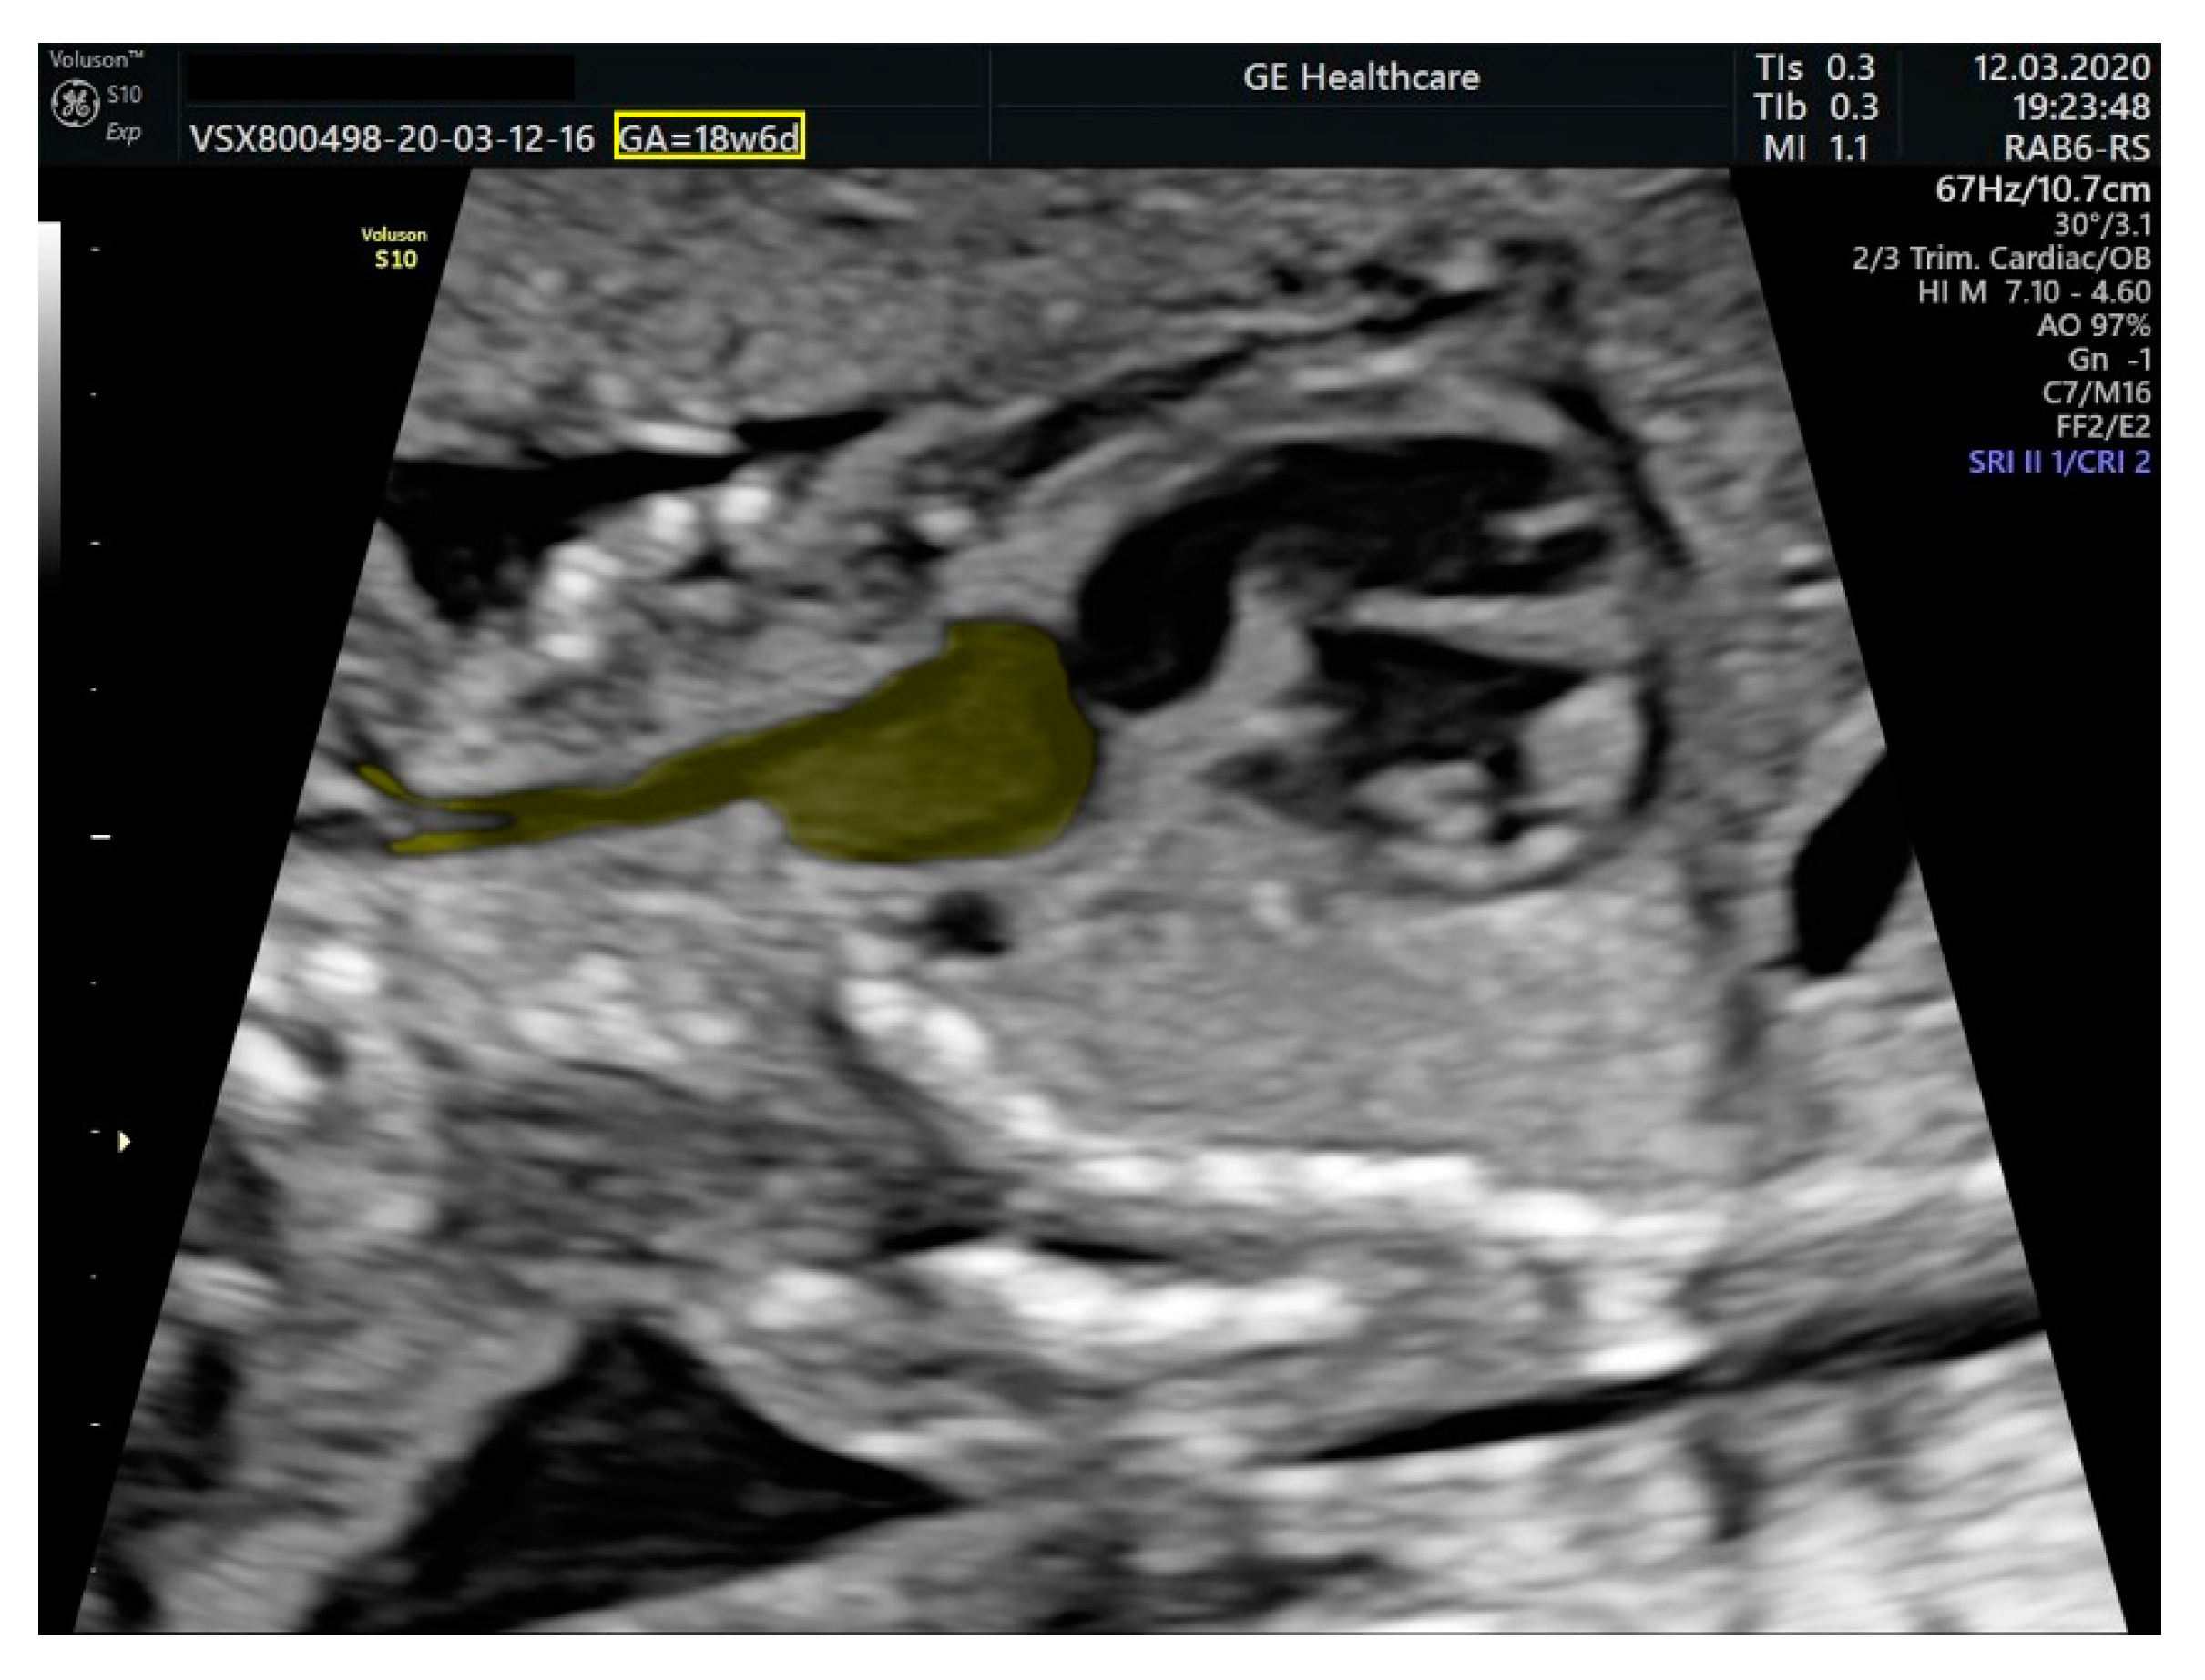

- ventricular septal defect, coarctation of the aorta, and a vascular formation located superior from the aortic arch with the appearance of an arteriovenous fistula;

- aneurysmal dilation located above the pulmonary trunk bifurcation and a dilated left common carotid artery with a retrograde flow;